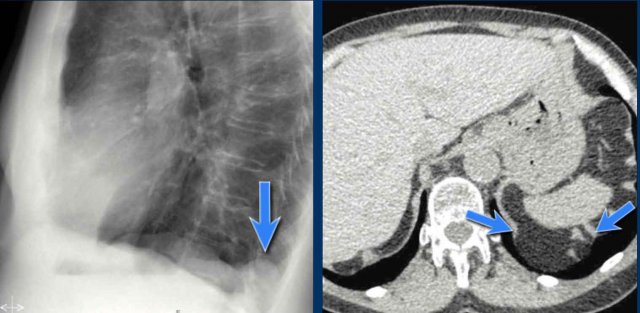

Bochdalek hernia Bochdalek hernia

Congenital Diaphragmatic Hernias

Bochdalek Hernia

• A Bochdalek hernia is a common incidental finding in adults and results from a posterior diaphragmatic defect(arrows).

• It typically contains retroperitoneal fat, is asymptomatic, and discovered incidentally.

• In rare cases, abdominal organs may herniate into the thorax.

• In neonates, large Bochdalek hernias may lead to pulmonary hypoplasia, which can be life-threatening.

Morgagni Hernia

• A Morgagni hernia is a less common congenital diaphragmatic hernia.

• It is located anteriorly, often presenting as a right-sided retrosternal mass.

• Like Bochdalek hernias, it may be asymptomatic or contain herniated abdominal contents.